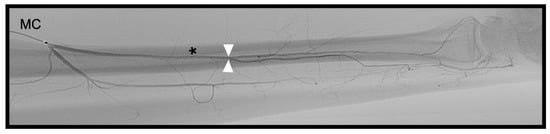

3.1. Palmar Radiocarpal Artery and Palmar Radiocarpal Arch (PRCA)

distance from the DCBUA to the styloid process of the ulnar (DCBUA = dorsal carpal branch of the ulnar artery).